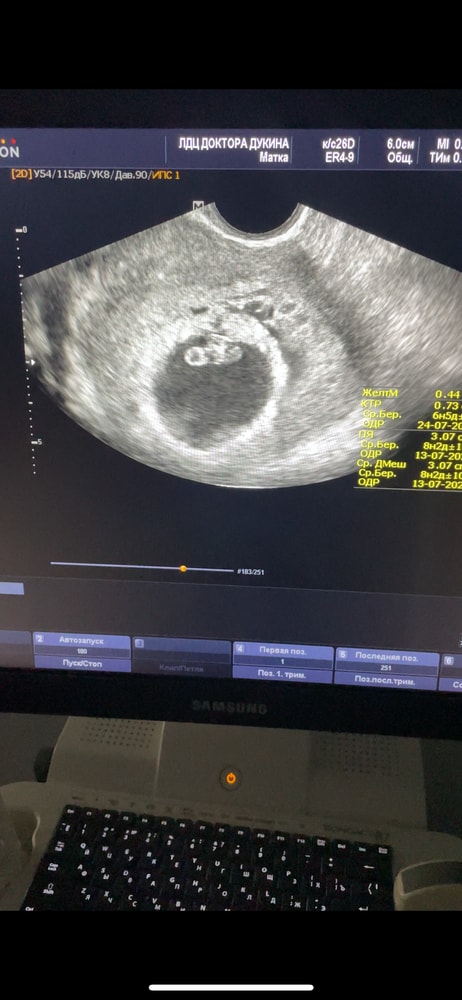

Расчет срока Б, ПДРВчера была на узи. По М у меня срок 6н 5дней. А внизу тогда почему еще написали 8 недель и 5 дней и одр другая дата? 😅 вчера была под эмоциями и забыла спросить у врача.

Скорее всего, 8 недель и 5 дней - это акушерский срок, считается от первого дня последней менструации, а 6 недель 5 дней - эмбриональный, от зачатия. Разница как раз около двух недель.

По размерам плодного яйца и крт эмбриона срок написали. Срок по которому все будут ориентироваться вам установят на 1 скрининге.

Alice, а, в заключении 6 н и 5 дней. Но на экране еще эта надпись и пдр другой 😅